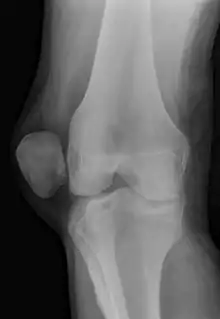

| X-ray showing a patellar dislocation, with the patella out to the side. | |

A patellar dislocation typically occurs when the knee is straight and the lower leg is bent outwards when twisting.[1][2] Occasionally, it occurs when the knee is bent and the patella is struck directly.[1] Commonly associated sports include soccer, gymnastics, and ice hockey.[2] Dislocations nearly always occur away from the midline.[2] Diagnosis is typically based on symptoms and supported by X-rays.[2]